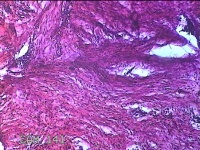

前胸部包块

性别

女

年龄

45岁

临床诊断

皮脂腺囊肿

一般病史

发现前胸部包块3个月余。

标本名称

大体所见

灰白暗红色组织2.2x1x0.8cm一块,表面带梭形皮肤2.2x1.3cm,皮下见包块1.8x1.2x0.8一块,切开包块呈实性,切面灰白粉红色,质软。

图1